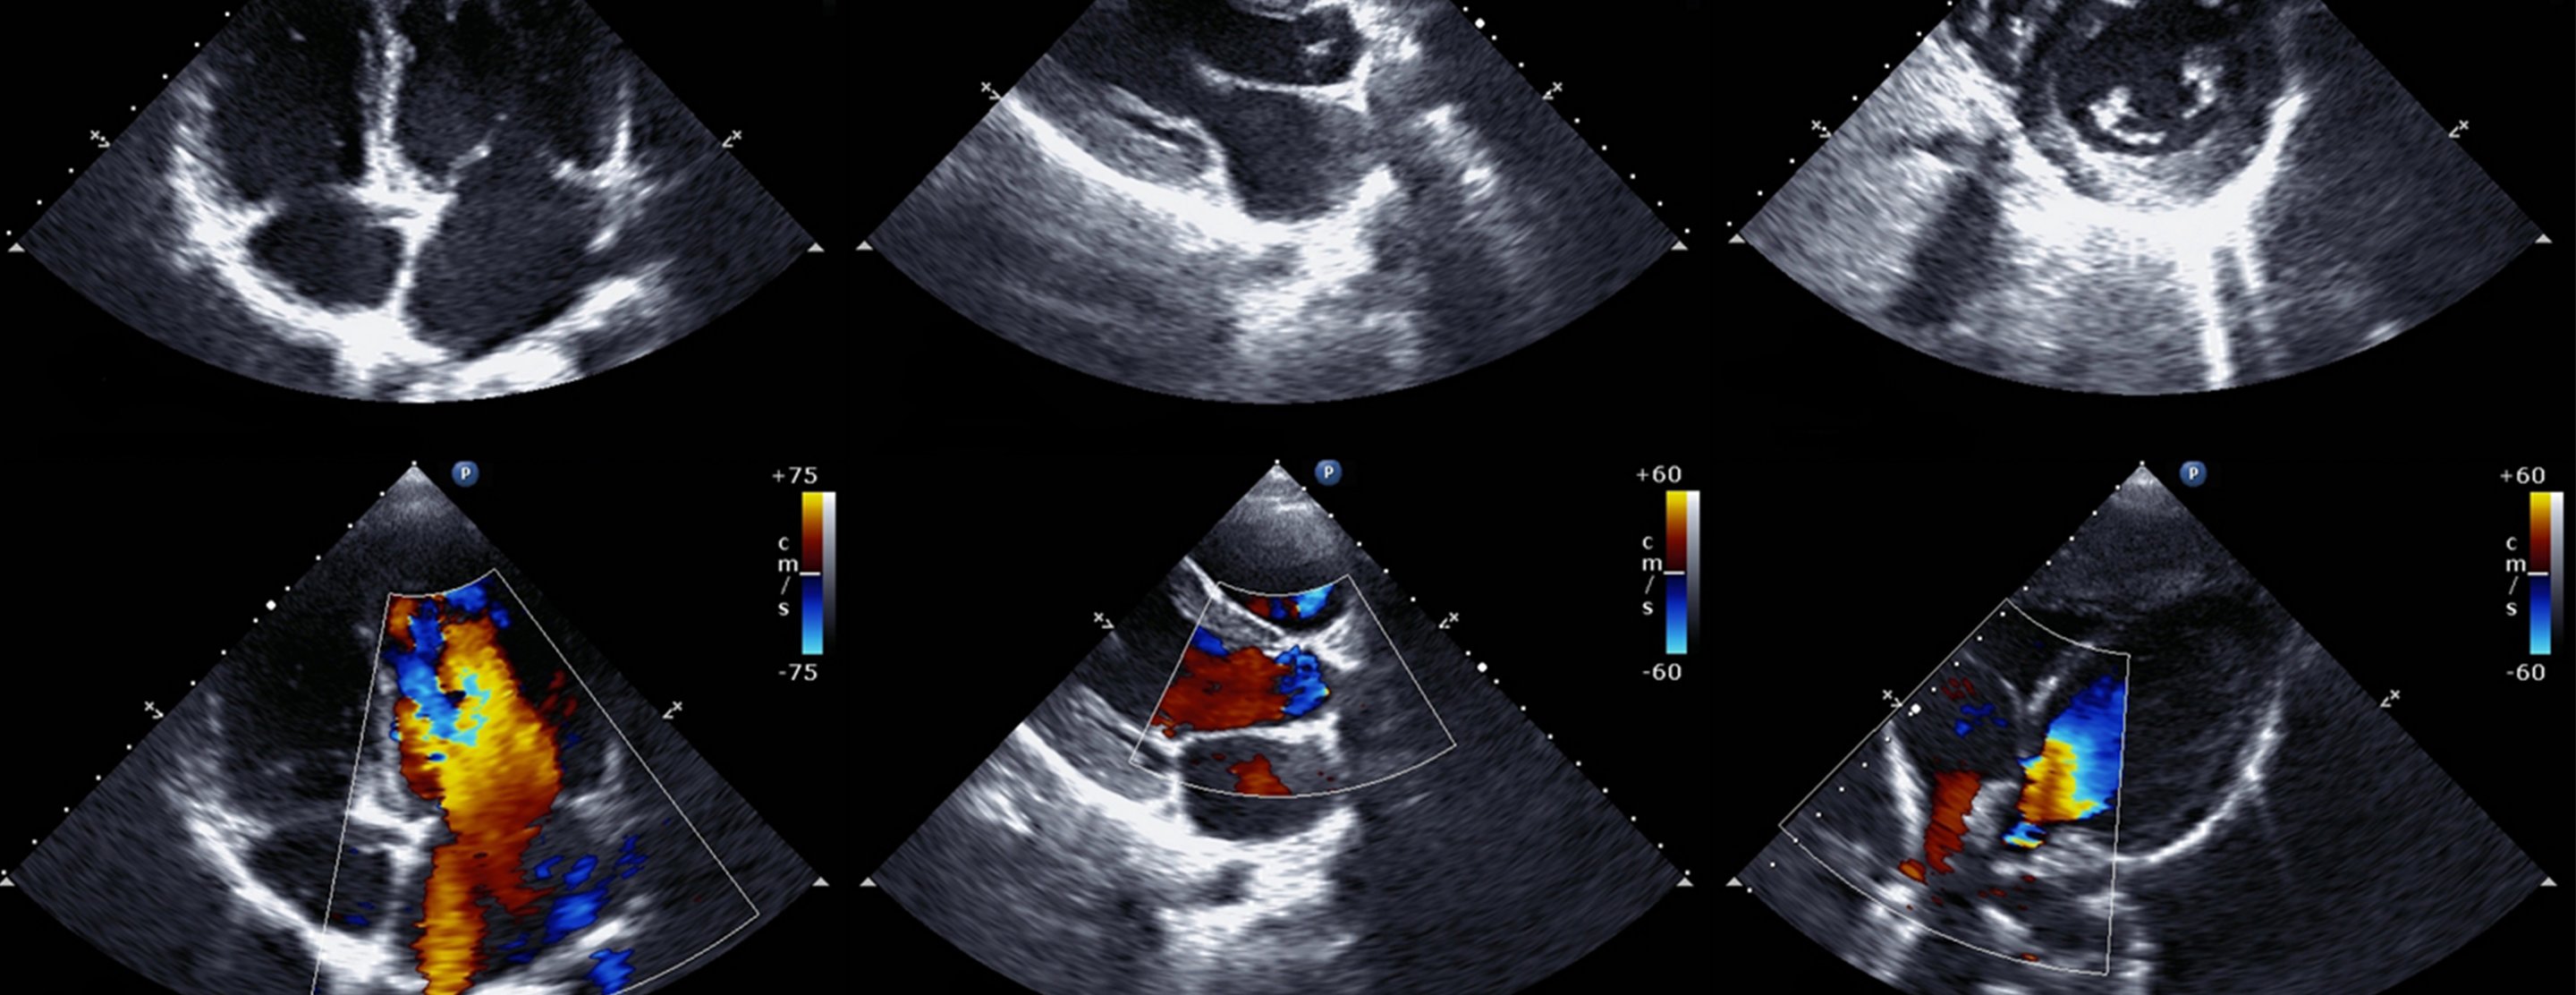

- Images can be two-dimensional or three-dimensional. The type of image will depend on the part of the heart being evaluated and the type of machine.

- A Doppler echocardiogram evaluates the motion of blood through the heart.

An echocardiogram shows the heart while it is beating. It also shows the heart valves and other structures.